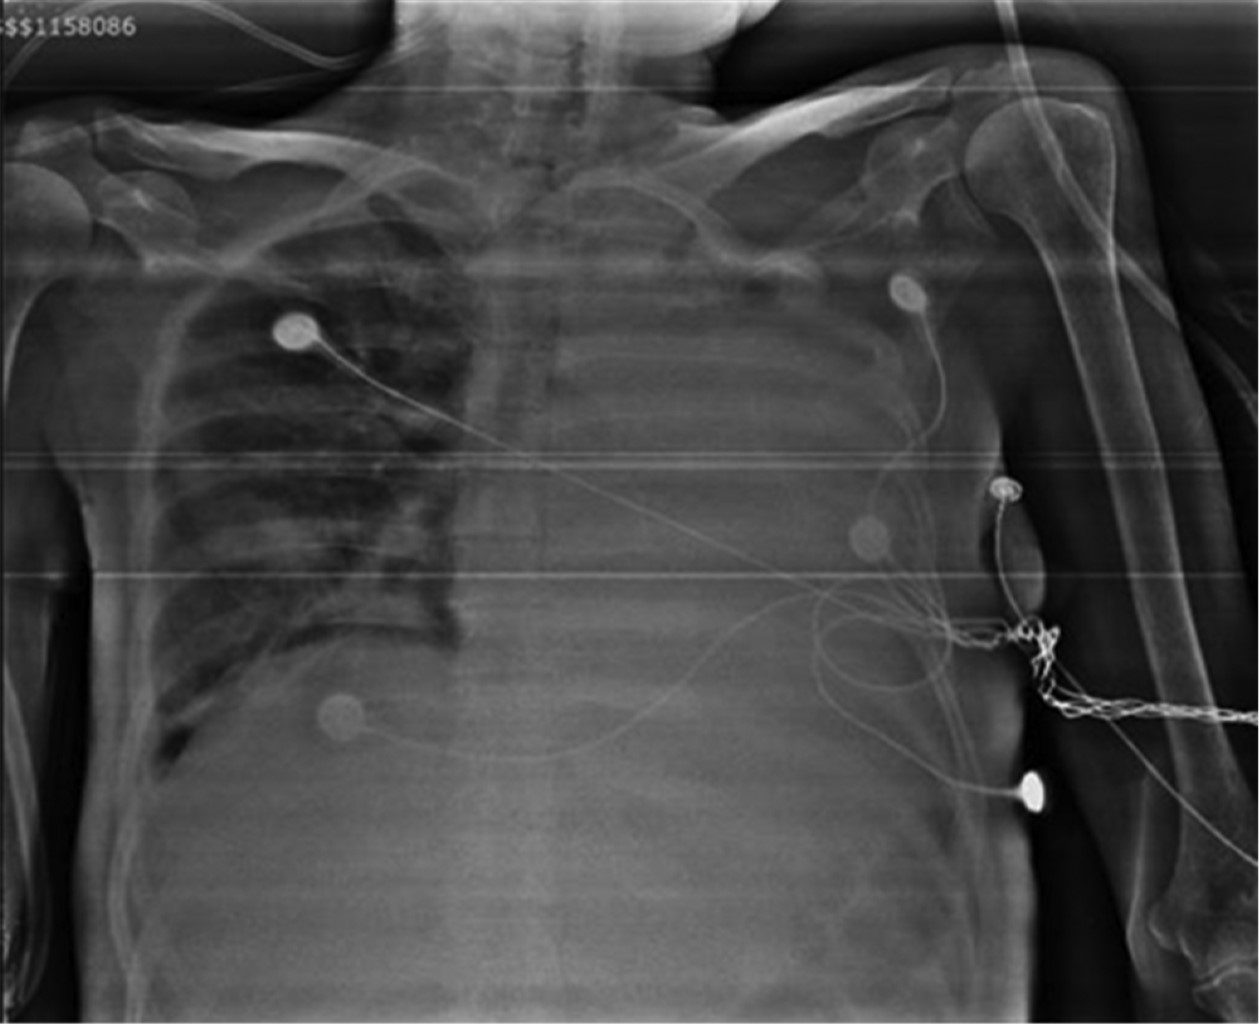

Mujer de 40 años de edad postnefrectomía secundario a absceso perirrenal, deterioro hemodinámico y respiratorio que requirió manejo en la Unidad de Cuidados Intensivos (UCI). La paciente presentó ventilación prolongada con necesidad de traqueotomía. Después de 38 días de estancia en la UCI se logra la decanulación de traqueostomía con éxito. Sin embargo, al cuarto día posterior a la decanulación presenta atelectasia completa del pulmón izquierdo sin datos de inestabilidad respiratoria (Figura 1). Las atelectasias completas se caracterizan radiológicamente por pérdida de la aireación pulmonar, radiopacidad de la región afectada, pérdida de la silueta cardiaca, ascenso de la cúpula diafragmática, desplazamiento de las estructuras mediastinales y tráquea de forma ipsilateral. Debido a las características del caso y las posibles complicaciones de manejo por medio de broncoscopia, se decide abordar de forma conservadora por medio de técnicas de fisioterapia pulmonar. Dentro del manejo fisioterapéutico se utilizaron técnicas de expansión torácica con apoyo de presión positiva con bolsa válvula mascarilla + válvula de presión positiva al final de la espiración (PEEP) de 10 cmH2O, tos asistida manual, fisioterapia de tórax para el manejo de secreciones y decúbito inspiratorio controlado (EDIC). Esta última técnica prioriza la ventilación hemipulmonar colocando en supralateral el pulmón a ventilar seguido de inspiraciones guiadas y finalizadas con espiraciones asistidas por compresión manual del tórax. Después de la radiografía de control a las seis horas (Figura 2) se decide la utilización de ventilación mecánica no invasiva durante la noche como manejo coadyuvante con una presión soporte 5 cmH2O y una PEEP de 5 cmH2O. Se logra el egreso hospitalario a los ocho días del evento con seguimiento médico y fisioterapéutico (Figura 3).

Figura 2